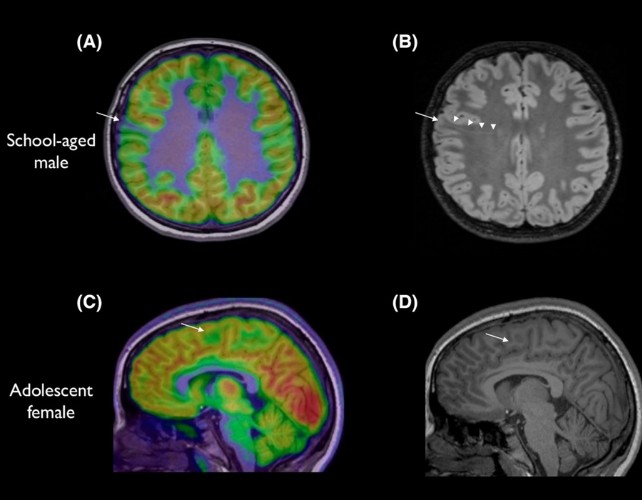

L’épilepsie a plusieurs causes, et environ trois cas sur dix proviennent d’anomalies structurelles du cerveau. Ces lésions passent souvent inaperçues sur les IRM — surtout les plus petites —, parfois cachées au fond d’un pli cérébral. L’étude a été dirigée par Emma Macdonald-Laurs, pédiatre neurologue au Royal Children's Hospital de Melbourne, qui explique que l’IA peut aider à repérer ces éléments et accélérer les décisions de traitement.

Les chercheurs ont entraîné l’IA sur des images du cerveau d’enfants pour trouver des lésions de la taille d’une myrtille ou moins. En combinant l’IRM et une autre technique appelée PET, le taux de réussite était de 94% dans un groupe et 91% dans l’autre. Sur 17 enfants du premier groupe, 12 ont subi une chirurgie pour enlever les lésions et 11 sont aujourd’hui sans crises.

80% des patients avaient préalablement eu une IRM normale. L’outil n’enlève pas le rôle des radiologues ou des médecins; c’est un détective qui aide à assembler les pièces du puzzle pour proposer une chirurgie potentiellement salvatrice. « Le tool ne remplace pas les radiologues ou les médecins de l’épilepsie, mais c’est comme un détective qui nous aide à mettre les pièces du puzzle ensemble plus rapidement afin d’offrir une chirurgie potentiellement salvatrice, » précise l’équipe. Des experts de King’s College London réagissent: « Ce travail est vraiment excitant et les résultats sont vraiment impressionnants. » Cependant, le physicien Konrad Wagstyl rappelle que le PET est coûteux et moins accessible que l’IRM et qu’il implique une dose de radiation.